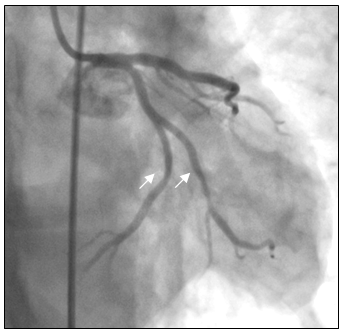

Tại cấp cứu bệnh nhân được chẩn đoán nhồi máu cơ tim cấp vùng hoành giờ thứ 2, block A-V độ 3, có chỉ định chụp mạch vành cấp cứu. Kết quả chụp mạch vành cho thấy hẹp nặng lan tỏa nhiều đoạn ở cả động mạch vành trái (hình 2a) và động mạch vành phải (hình 2b).

Hình 2a: Dấu mũi tên trắng cho thấy nhiều chổ hẹp ở nhánh LCX, OM và LAD